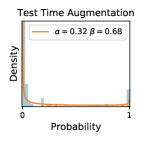

5.1 Distribution of Uncertainty Scores

Distribution of Uncertainty Scores Across Different Severity Levels As explained in Section 3, each uncertainty metric essentially defines an order/ranking among the data points. We conducted an analysis to better understand what data will be assigned high uncertainty under a particular uncertainty metric . Picking out the highest ranked data points (), we calculated the ratio of data points from each SL. Figure 4 summarizes the results as box plots for the Kaggle-DR and the Messidor-2 datasets; additional detailed statistics can be found in Table S.1 in the supplementary materials. From the plot and table, SL1 & SL2 examples account for a higher proportion among the top-ranked uncertain examples across the three ensemble methods. This finding matches our intuition that incipient disease examples (SL1 & SL2) are more likely to be considered uncertain by ensemble methods due to their ambiguity.

Comparing the three ensemble methods in Figure 4, the stacking ensemble method has the highest ratios of SL1 & SL2 data among the high-uncertainty examples it identified under both mean and var. TTA showed slightly better performance than MC-dropout but still falls behind the stacking ensemble method. Considering the fact that SL0 examples accounted for the majority of the dataset, the stacking ensemble method was much more precise (specific) in selecting truly ambiguous data points that were difficult to classify. From Figure 3, we can also see that the stacking ensemble method greatly outperformed the other two methods in finding false negatives under both mean and var uncertainty metrics.

In contrast, the MC-dropout method showed the worst overall performance among the three, as it can be seen from the high ratios of SL0 examples among the uncertain negatives in Figure 4. The histograms in Figure 2 provides another perspective to look into the phenomenon, where a decent proportion of MC-dropout model’s predictions on SL0 inputs entailed low confidence (far from 0 or 1), which from another angle explained why MC-dropout was less specific in terms of lower FNP; many no-DR inputs (i.e. SL0) were erroneously assigned high uncertainty by MC-dropout models.

It is still an open question why the evaluated MC-dropout networks signaled relatively high uncertainty on SL0 & SL3 & SL4 data that are less likely to be ambiguous. We conjecture that much of the “uncertainty” indicated by disagreement among test-time dropout samples actually reflects the stochastic nature of dropout networks rather than the real decision uncertainty associated with the data. It is worth noting that the MC-dropout model we evaluated was not weak per se; they all achieved above Area Under Curve (AUC) scores on test sets. The weakness of individual test-time samples (which explains their low-confidence predictions on SL0 & SL3 & SL4) might have been hidden when they are aggregated into an ensemble—a well-known advantage of ensemble learning. Our results suggested that the uncertainty information given by implicit ensemble methods such as MC-dropout and TTA might not be as reliable as that from explicit ensemble approaches (e.g., stacking ensembles). Similar findings on MC-dropout can be found in some previous papers [1].